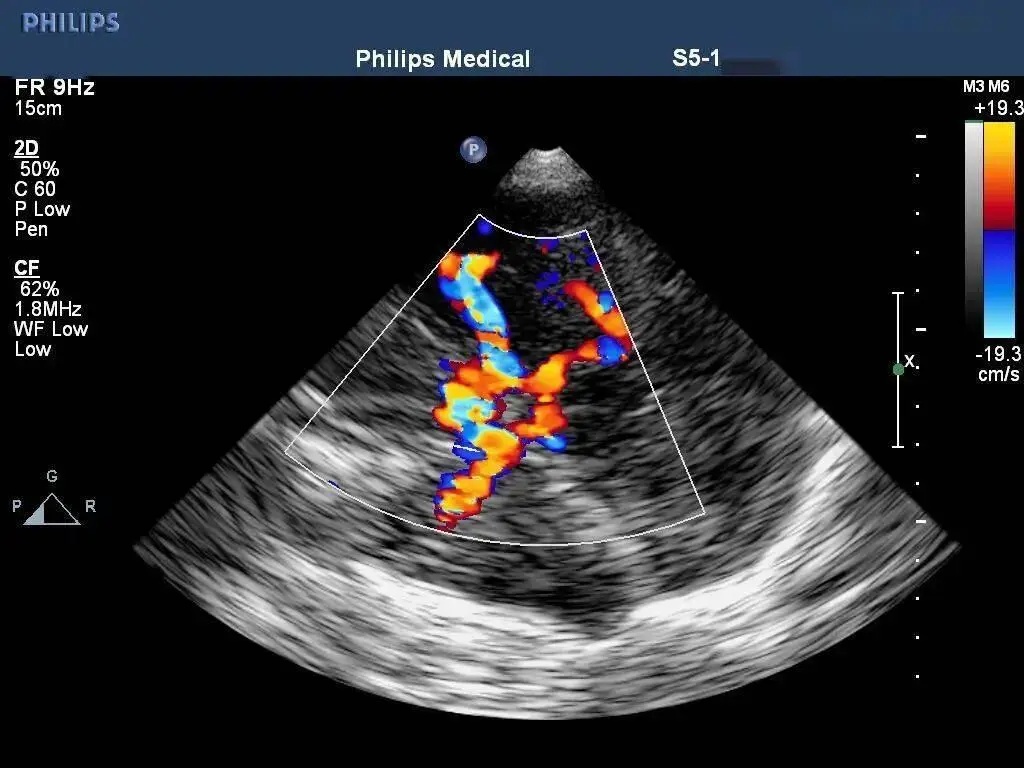

经枕骨大孔平面检查:双侧椎动脉与基底动脉彩色血流成像